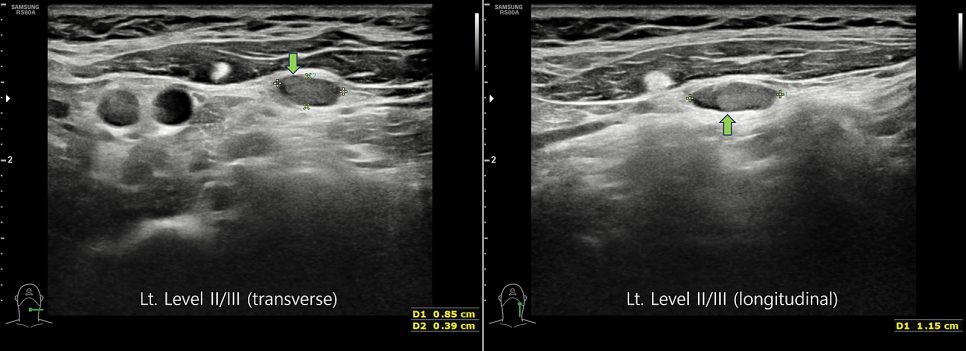

림프절 전이를 알아보기 위해 경부 림프절 초음파 검사를 통해 관찰해 보았습니다.

왼쪽 2구역 3구역 경계 부위에 있는 림프절로, 이 부분에서도 잿빛 덩어리가 굳어 있는 것을 볼 수 있어요.갑상선암 전이의 소견입니다.